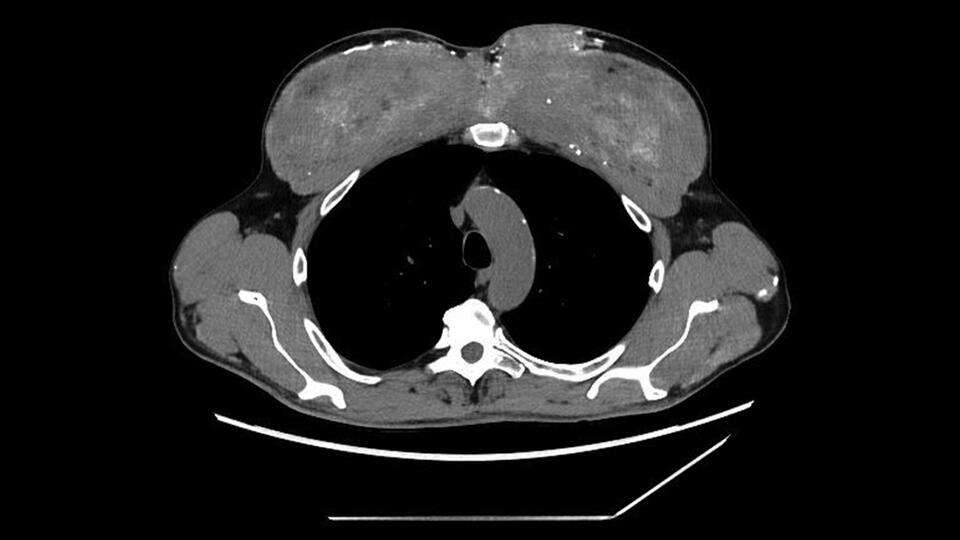

The Signal Wire

Breaking News - Health Talk - When Normal Oxygen Levels Mask a Deeper Crisis Today’s Signal Wire feature examines a medical case that challenges one of healthcare’s most trusted metrics. Oxygen saturation: Normal. Lungs: Clear. Cardiac function: Stable. Laboratory findings: Unremarkable. Yet the patient was gasping for air. When supplemental oxygen was administered, saturation levels declined rather than improved. This is not routine variation. This is a signal disruption. Cases like this move medicine from protocol to pattern recognition. Several physiological explanations may account for this anomaly: Dyshemoglobinemia Toxic Environmental Exposure Cellular Hypoxia Equipment–Environment Interaction This case highlights a critical truth in modern medicine: Data points are measurements not conclusions. As healthcare integrates artificial intelligence, wearable biometrics, and predictive modeling, the volume of available data continues to grow. However, signal interpretation remains essential. When multiple individuals in a shared environment experience physiological distress, the pattern itself becomes clinically significant. This is not merely a patient event. It is a potential signal cluster. But predictive systems depend on recognizing when data appears normal while physiology is not. Sometimes oxygen is present. But the system is not functioning. That distinction can determine outcomes. Follow @thesignalwire for continued Signal Wire briefings analyzing the patterns reshaping modern healthcare. #BreakingNews #getinspired #Inspiration #HealthNews #thesignalwire #NewsBreaks #Mystery #MedicalMystery #AI